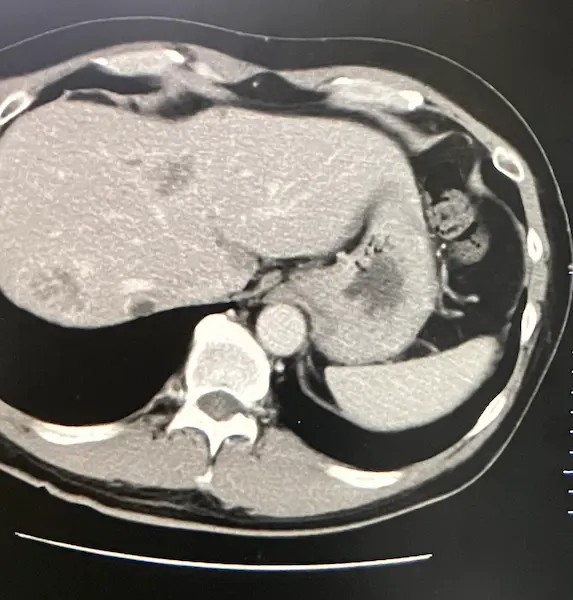

CT画像では、がんは小さくなっていて経過良好です。

CT検査の結果は良好でした。 肝臓に転移したがんが、目に見えて小さくなっていたのです。

肝臓に転移したがんがさらに小さくなっていました。それを証明するかのように腫瘍マーカーも下がっていました。

またCT画像では、がんが白く石灰化しているのが確認できました。腫瘍マーカーは7。ついにひと桁まで下がりました。

抗がん剤治療の効果が出ています。